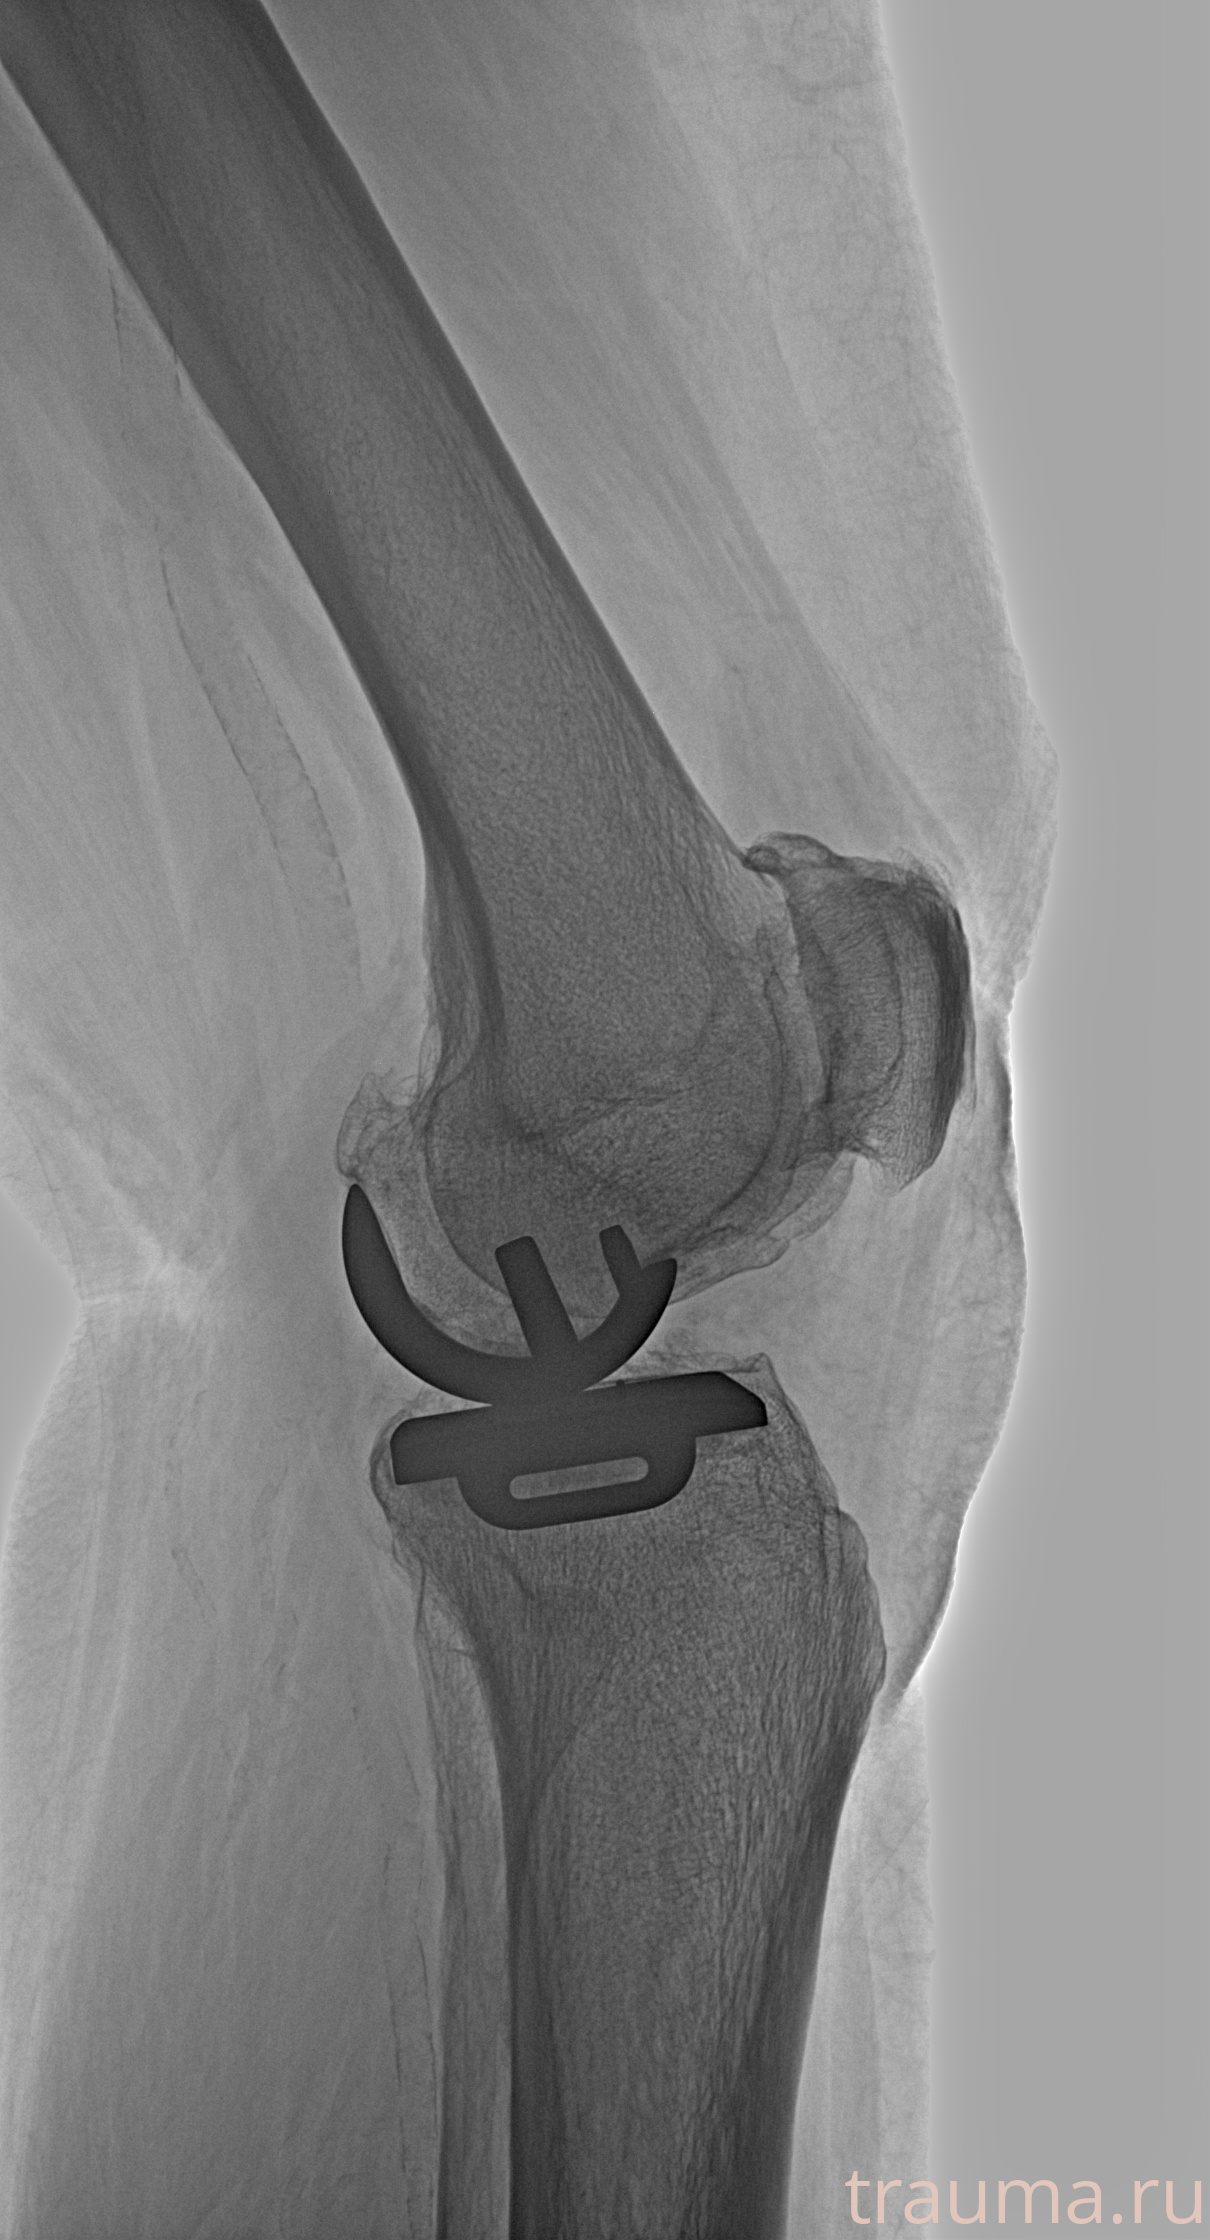

Правый

Рентгенограммы